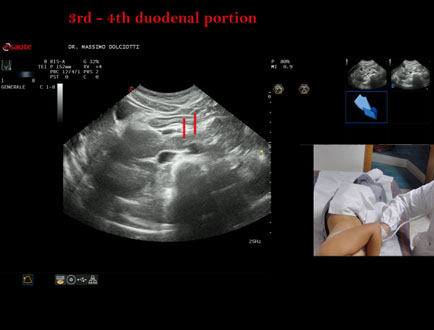

Data inserimento: 21/03/2025

Ecografia del: 10/03/2025

Strumento: Esaote MyLab Eight

Sonda: Convex Multifrequenza 1-8 MHz

Età Paziente: F 81 anni

Motivazione dell'esame: tdolori addominali.

Commento all'esame: le immagini ed il video documentano la 3° e la 4° porzione del duodeno e l'angolo del Treitz.

Conclusioni: 3° e 4° porzione duodenale ed angolo del Treitz (3rd and 4th duodenal portion and Treitz angle ).

Presentazione: Dr. Massimo Dolciotti - Ancona

Elaborazione digitale: Andrea Dini - Ancona